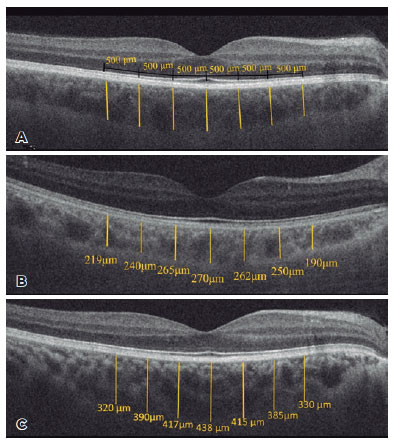

All patients underwent OCT and EDI-OCT using the Cirrus Zeiss 5000 Zeiss. Choroidal thickness, central macular thickness, and ganglion cell thickness were compared between both groups. Choroidal thickness was measured by two experienced ophthalmologists (ŞGK and RK) who were blinded to the sessions using manual calipers of Cirrus HD-OCT software, after which the measurements were averaged for analysis. Measurements were made at 7 points: the subfovea and temporal and nasal quadrants at 500 μm intervals up to 1500 μm from the fovea. Choroidal thickness was measured from the outer edge of the hyper-reflective RPE to the inner sclera (Figure 1).

Group 1 had a thicker choroid compared to Group 2 at all measurement points. Mean subfoveal choroidal thickness was 370.60 ± 73.4 μm and 331.48 ± 62.1 μm in Groups 1 and 2, respectively, with a significant difference having been found between the two groups (p=0.011). Significant differences in the measurements made from the fovea at 500 μm nasal and temporal and 1000 μm nasal were observed between both groups (p=0.009, 0.043, and 0.019, respectively). However, no significant differences in the other measurements were observed (p>0.05). Interobserver measurements were performed at the 95% confidence interval (Table 2).